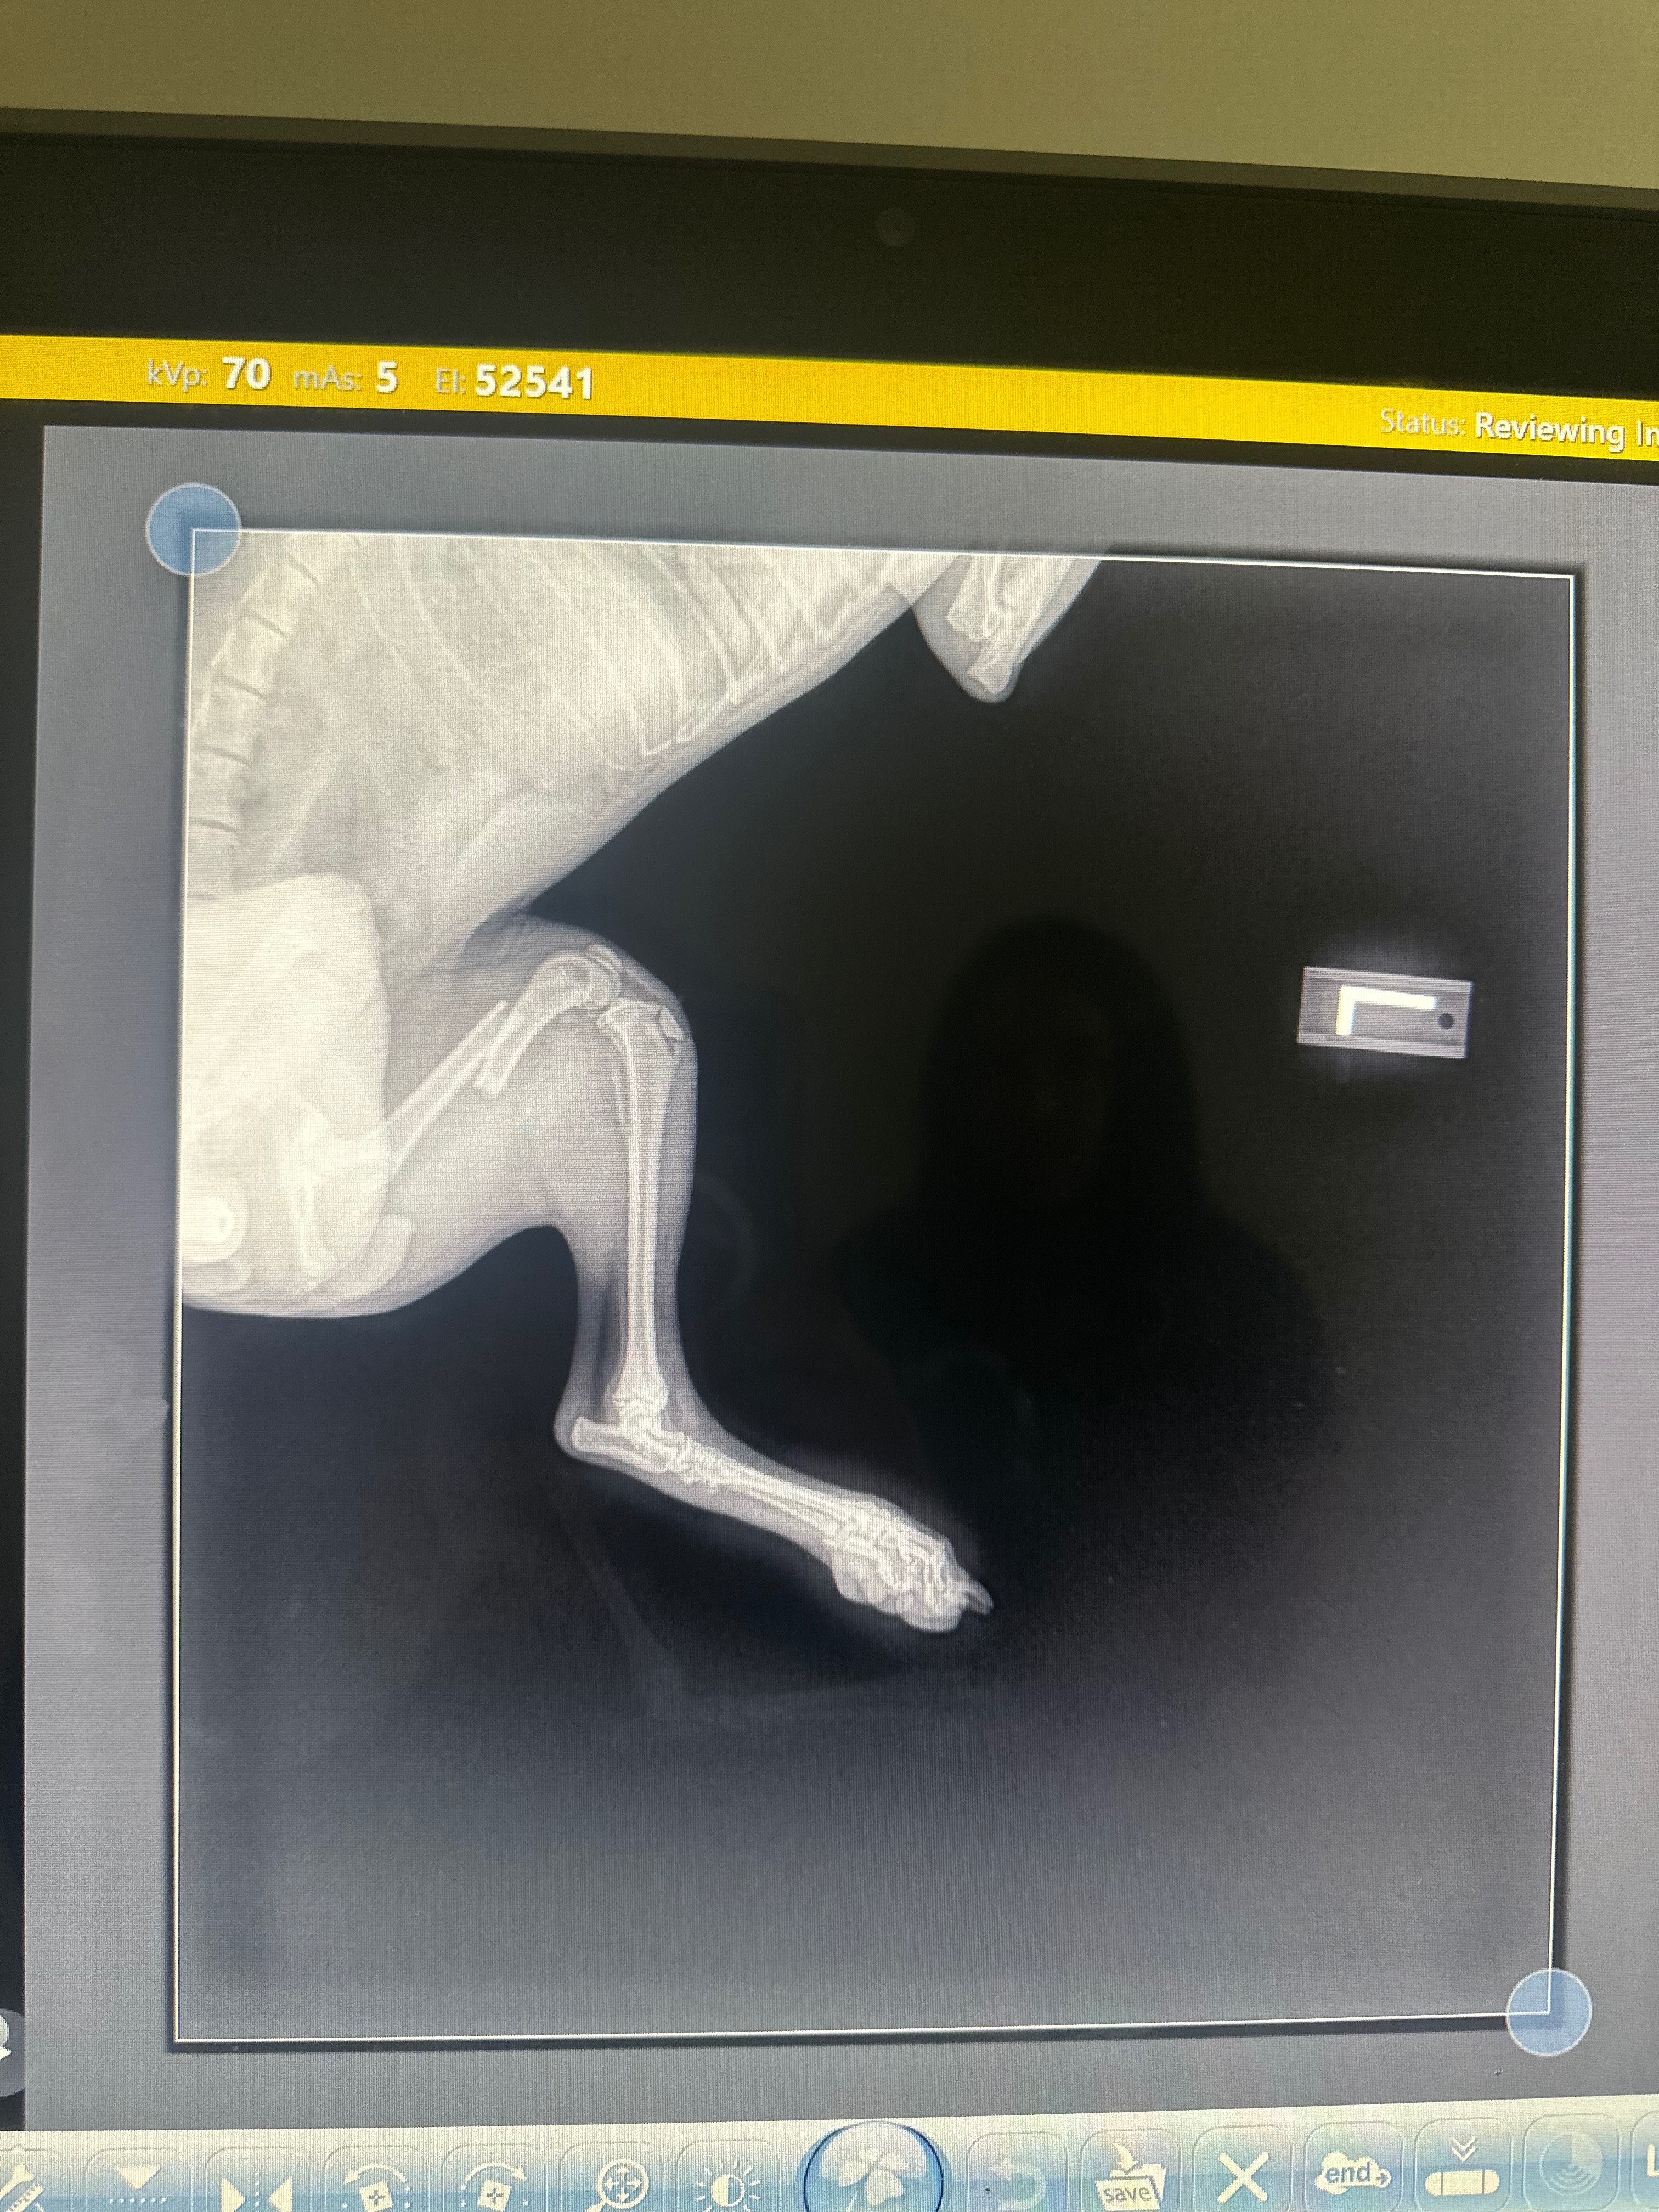

Help Baby Aiko undergo surgery for a Fractured leg.

my little baby Aiko is 6mo. she fell from the couch and fractured her femur bone. it broke my heart when i heard her cries. shes only 8lbs. shes in pain and she got pains meds for the time being. the next step would be surgery to repair the fracture and its really expensive.